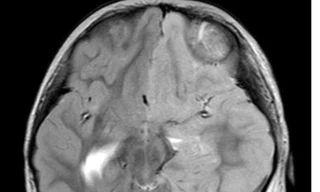

TPO - Cho rằng con học nhiều nên bị đau đầu gia đình không đưa đến bệnh viện thăm khám, hơn 1 tháng sau bé gái 12 tuổi rơi vào tình trạng yếu nửa người bên trái. Tại bệnh viện, bác sĩ xác định trẻ bị đột quỵ do vỡ dị dạng mạch máu não.